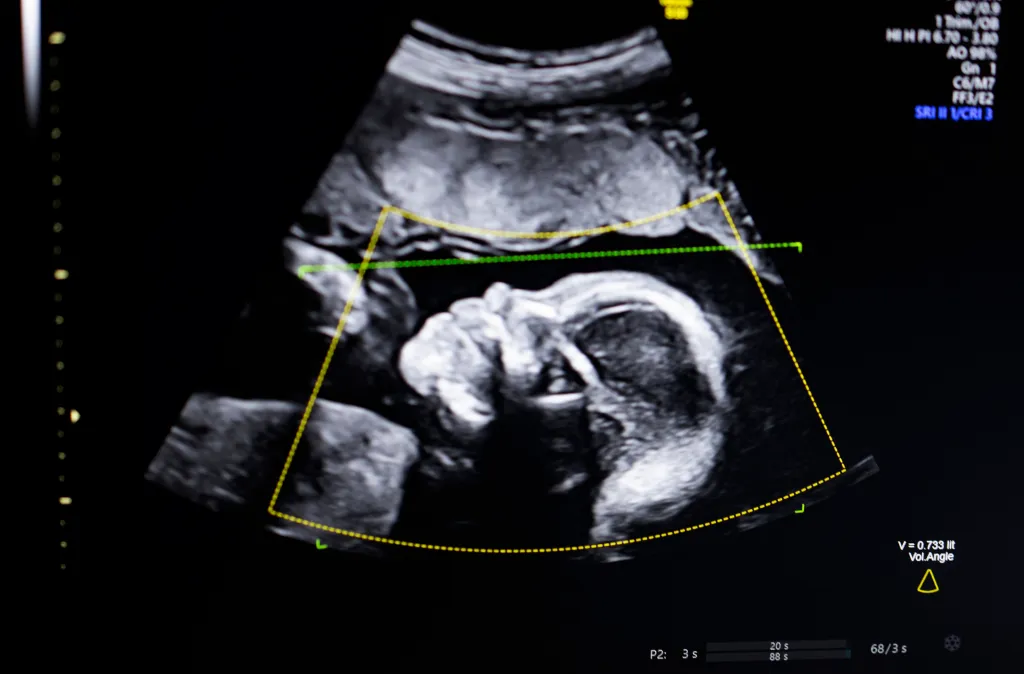

Produkti i BioticsAI është projektuar për të ndihmuar profesionistët e shëndetit gjatë ekzaminimeve prenatale, duke analizuar në kohë reale cilësinë e imazheve të ultrazërit dhe duke sinjalizuar nëse pamjet anatomike janë të plota dhe të përshtatshme për vlerësim. Në praktikë, kjo do të thotë më pak rrezik për skanime jo të sakta dhe më shumë mbështetje për mjekët dhe teknikët, sidomos në ambiente me burime të kufizuara ose me staf më pak të specializuar. Teknologjia përdor modele të trajnuara mbi një numër të madh imazhesh fetale, me synimin për të standardizuar cilësinë e ekzaminimeve dhe për të reduktuar variacionet që vijnë nga përvoja e operatorit. Ky aspekt shihet si veçanërisht i rëndësishëm në kujdesin prenatal, ku zbulimi i hershëm i anomalive mund të ketë ndikim vendimtar në trajtimin dhe ndjekjen e shtatzënisë.

Themeluesit e BioticsAI e kanë përshkruar produktin si një mjet ndihmës, jo si zëvendësim të gjykimit mjekësor. Qëllimi, sipas tyre, është të rritet besueshmëria e ekzaminimeve dhe të lehtësohet puna e profesionistëve shëndetësorë, duke u dhënë atyre sinjale të qarta kur një skanim duhet përsëritur ose përmirësuar. Miratimi nga FDA përfaqëson gjithashtu një moment të rëndësishëm për industrinë e AI-së në shëndetësi. Ai tregon se teknologjitë e bazuara në inteligjencë artificiale po kalojnë gjithnjë e më shpesh nga faza e prototipit drejt përdorimit të rregulluar dhe të verifikuar klinikisht. Në një sektor ku siguria dhe besimi janë thelbësore, ky hap shihet si sinjal pozitiv për startup-et që synojnë të sjellin zgjidhje të reja në praktikën mjekësore.